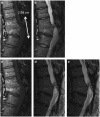

The efficacy of olfactory mucosal autografts (OMAs) for chronic spinal cord injury (SCI) has been reported, but there is no report documenting electrophysiological conductivity via the emergence of motor evoked potentials (MEPs). We report the case of a 39-year-old man with chronic, complete SCI at T8, who exhibited MEPs after OMA transplantation, and, with intensive rehabilitation, was ultimately able to ambulate with short leg braces and Lofstrand crutches. The initial injury occurred in a motor vehicle accident in November 1999 and resulted in a complete loss of sensorimotor function below T8. OMA transplantation to the injury site was performed in March 2010 in combination with intensive pre- and postoperative rehabilitation. The patient exhibited voluntary electromyograph (EMG) activity and MEPs at 96 and 144 weeks after transplantation and he was was ambulatory with short leg braces and Lofstrand crutches at 144 weeks after transplantation. We were able to elicit MEPs after OMA with intensive rehabilitation. To our knowledge, this is the first report of recovery of electrophysiological conductivity in the spinal cord after any type of treatment for chronic, complete SCI.